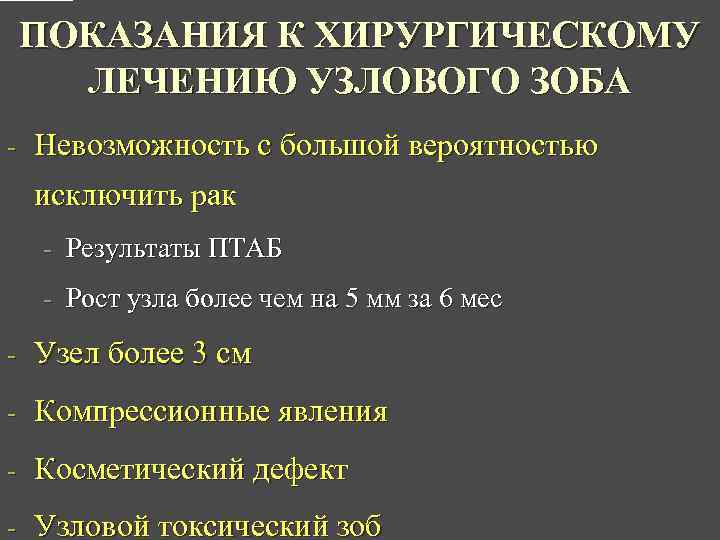

ПОКАЗАНИЯ К ХИРУРГИЧЕСКОМУ ЛЕЧЕНИЮ УЗЛОВОГО ЗОБА - Невозможность с большой вероятностью исключить рак - Результаты ПТАБ - Рост узла более чем на 5 мм за 6 мес - Узел более 3 см - Компрессионные явления - Косметический дефект - Узловой токсический зоб